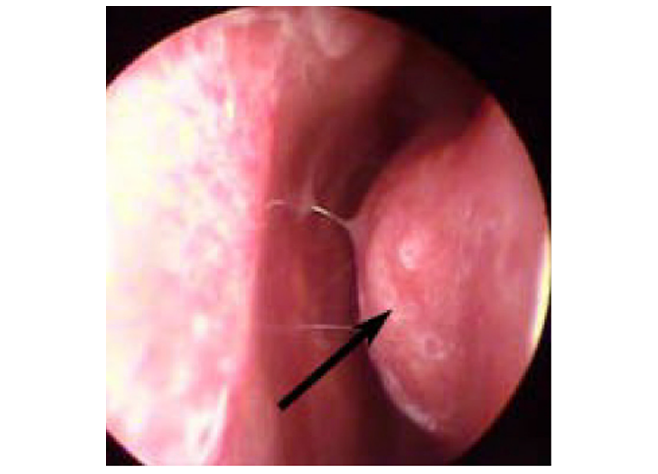

Un manipolo specifico viene inserito nella sottomucosa del turbinato ipertrofico, in genere il turbinato inferiore, il cui tessuto in eccesso subisce un processo di vaporizzazione. Si ottiene in tal modo uno spazio maggiore nella fossa nasale corrispondente, senza la necessità di alterarne l’architettura osteocartilaginea. La procedura è quasi sempre bilaterale.

Intervento in Radiofrequenze

Al termine del trattamento con radiofrequenza dell’ipertrofia dei turbinati, lo spazio respiratorio nasale risulta notevolmente aumentato.